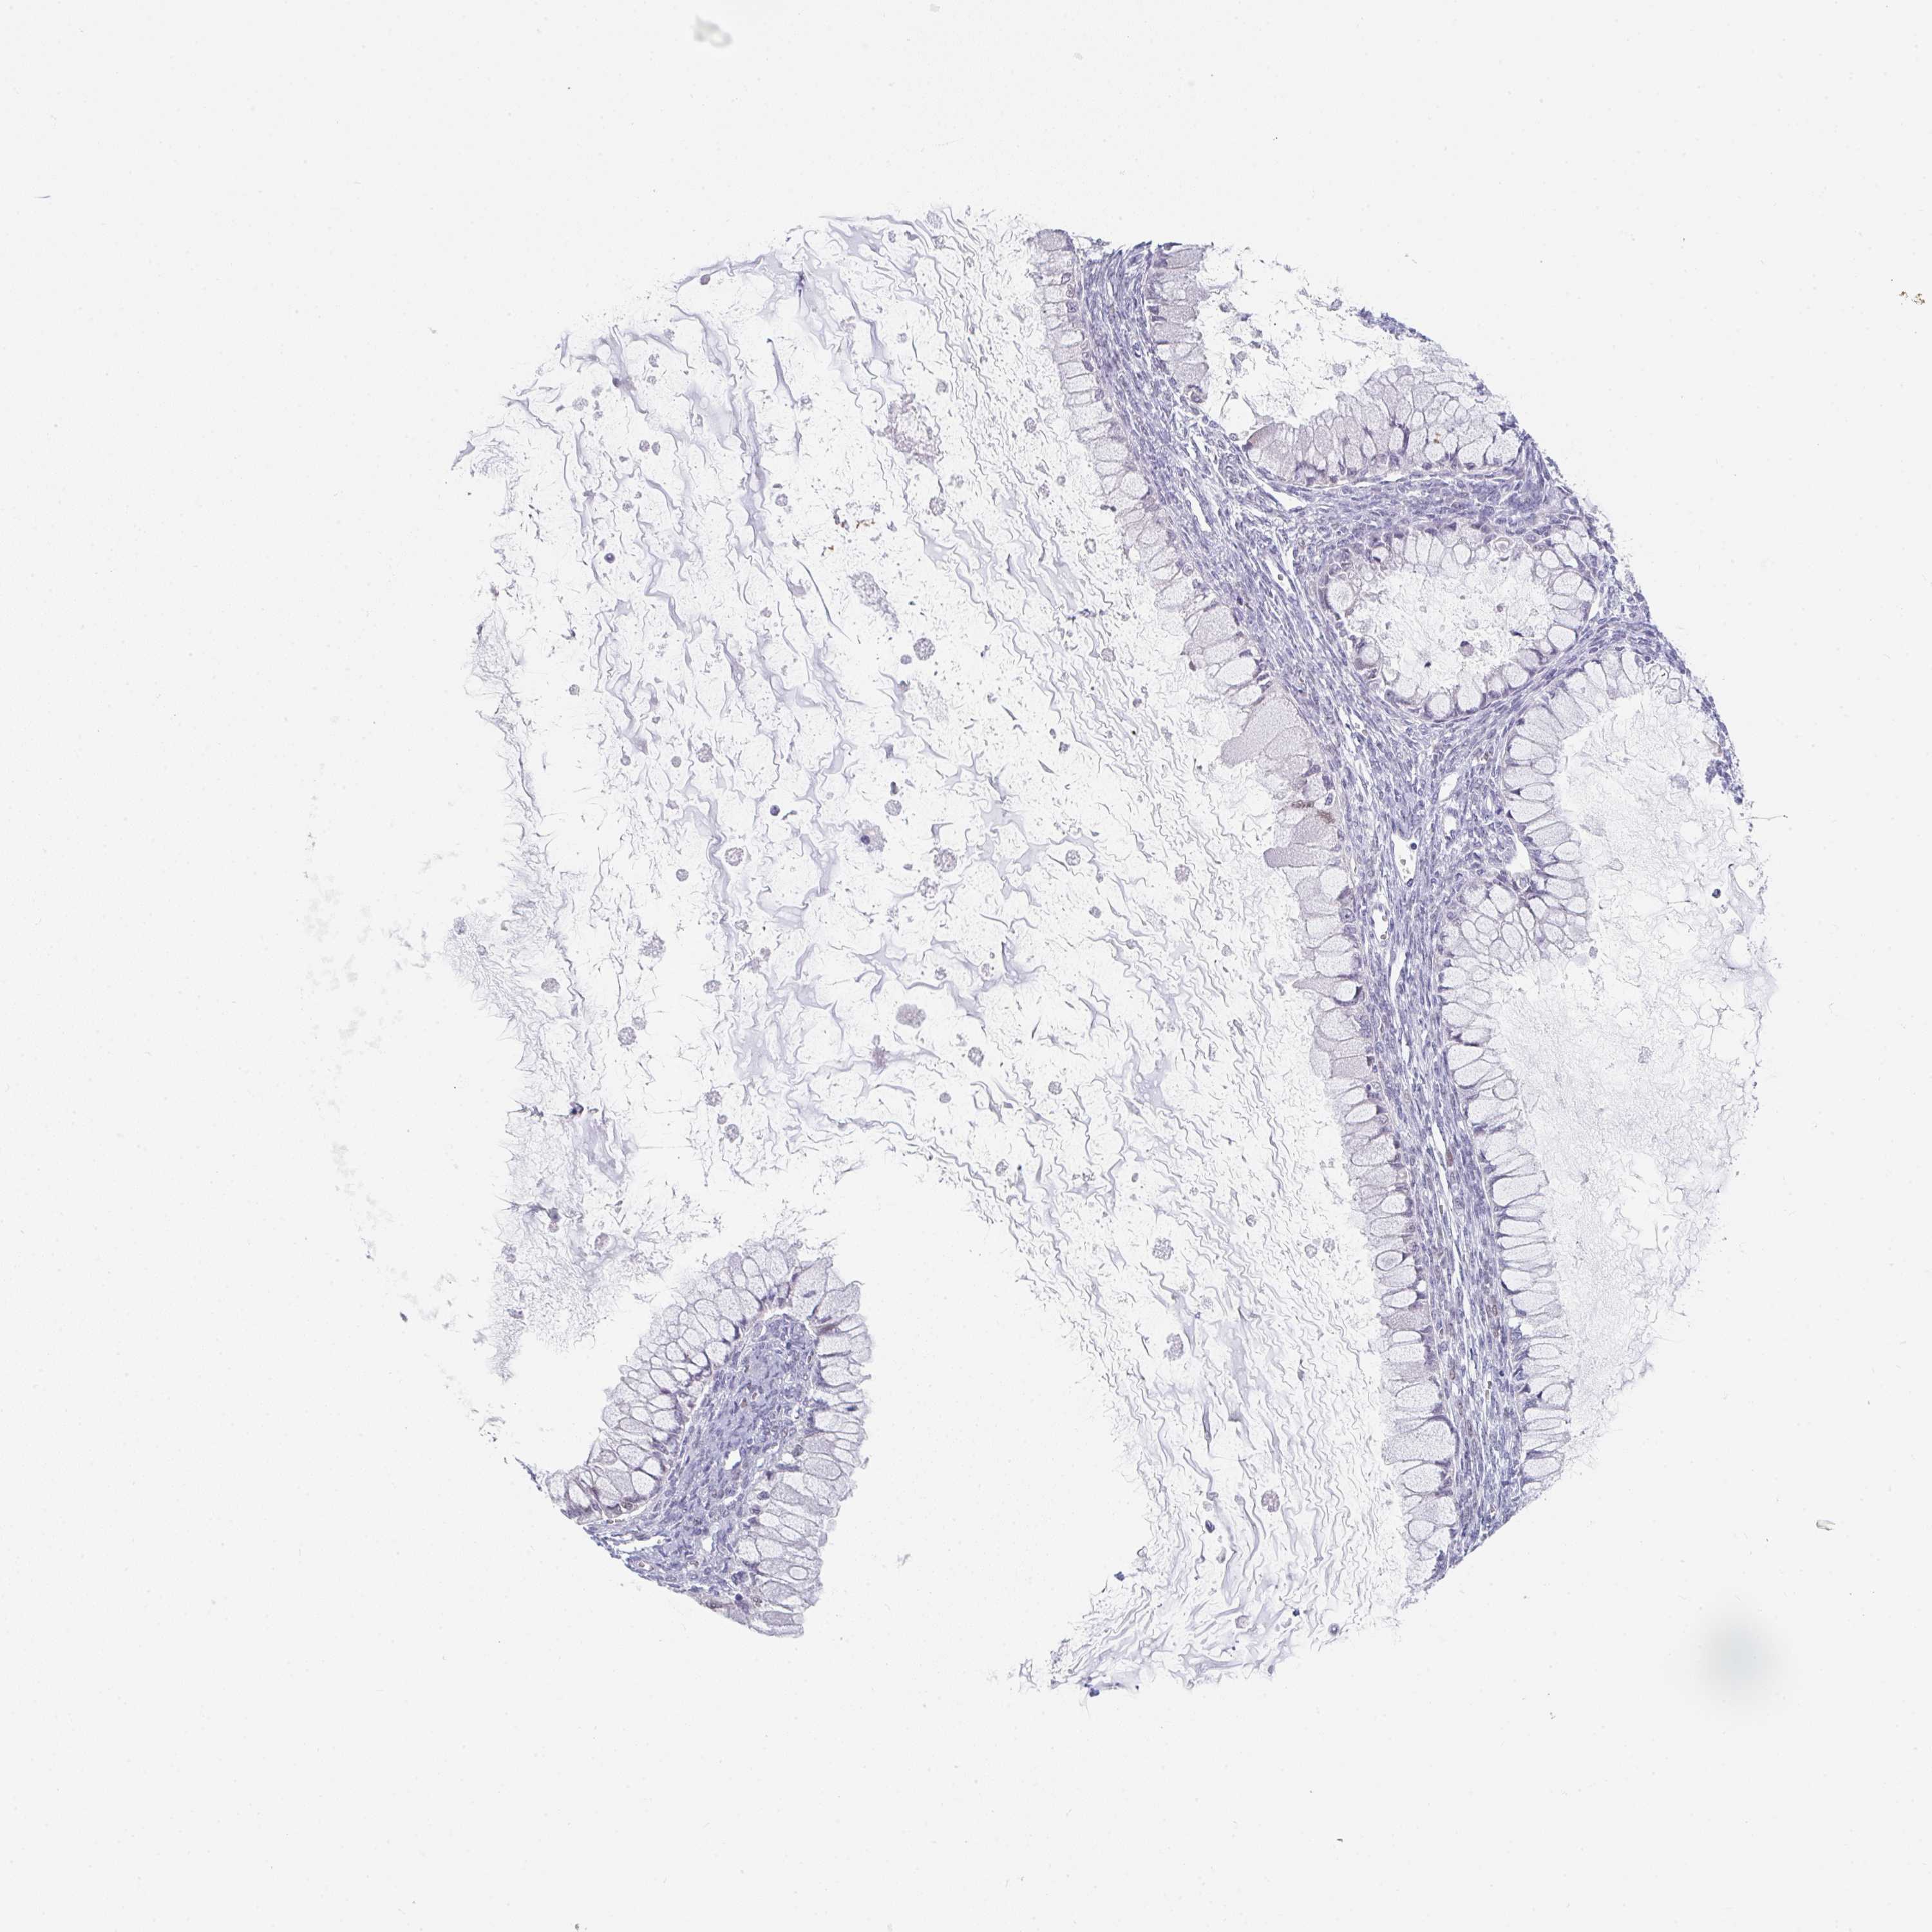

OVARIAN CANCER - Protein expressioni

A mouse-over function shows sample information and annotation data. Click on an image to view it in a full screen mode. Samples can be filtered based on level of antibody staining by selecting one or several of the following categories: high, medium, low and not detected. The assay and annotation is described here.

Note that samples used for immunohistochemistry by the Human Protein Atlas do not correspond to samples in the TCGA dataset.

Antibody stainingi

Antibody staining in the annotated cell types in the current human tissue is reported as not detected, low, medium, or high, based on conventional immunohistochemistry profiling in selected tissues. This score is based on the combination of the staining intensity and fraction of stained cells.

Each image is clickable and will lead to virtual microscopy that enables deeper exploration of all samples and also displays staining intensity scores, fraction scores and subcellular localization as well as patient and tissue information for each sample.

Antibody HPA054497

Staining

High

Medium

Low

Not detected

Intensity

Strong

Moderate

Weak

Negative

Quantity

>75%

75%-25%

<25%

None

Location

Nuclear

Cytoplasmic/membranous

Cytoplasmic/membranous,nuclear

Cystadenocarcinoma, serous, NOS

Cystadenocarcinoma, mucinous, NOS

Carcinoma, endometroid